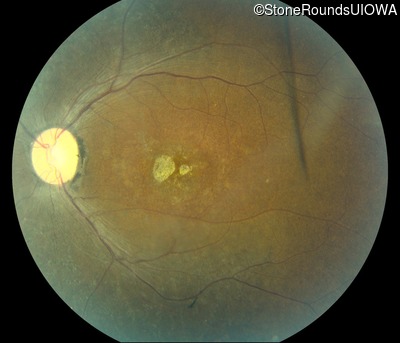

This 47 year old woman was born with a supernumerary digit on the ulnar side of both hands. As a young child, her best corrected visual acuity was completely normal. She had no difficulties with her vision until age 30 when her visual acuity could no longer be corrected to 20/20 and she began to notice some night blindness.

The clinical features supporting the diagnosis of Bardet Biedl syndrome in this patient include: bone-spicule-like pigmentation, narrowed arterioles and macular atrophy on ophthalmoscopy; photoreceptor loss on OCT; ulnar polydactyly, obesity, abnormal cognition, hypertension; and, normally sighted parents.